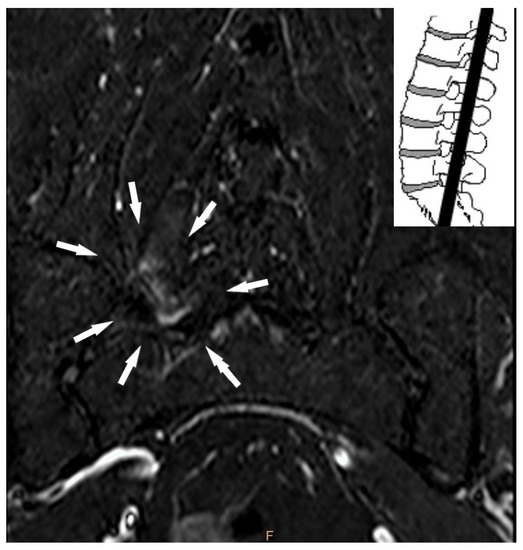

- Lumbar facet joint edema;

| Lumbar facet joint edema | Absent | 53 | 58.9 |

| Present | 37 | 41.1 | |

| Lumbar facet joint edema (present) | 1.858 | 0.617 | 0.003 | 6.412 | 1.913 | 21.492 |